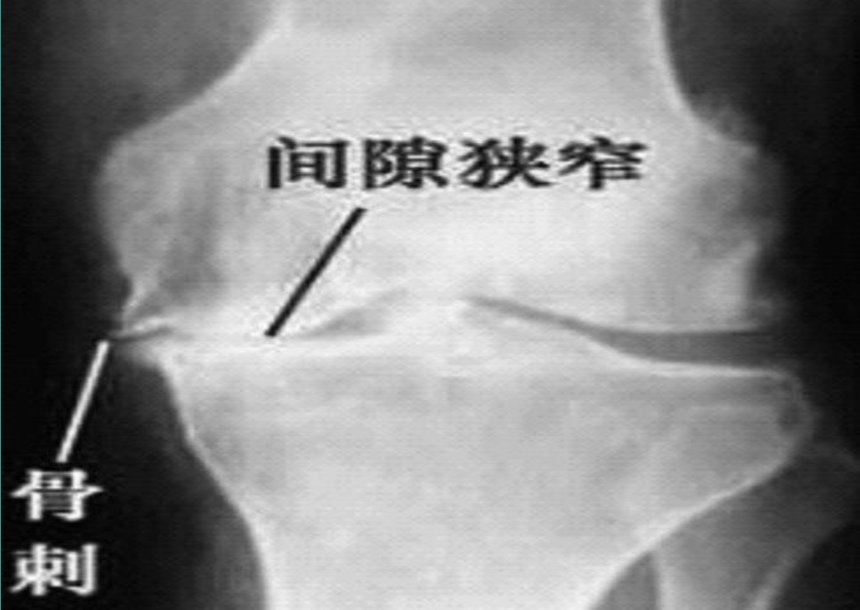

X线检查基本特征1.关节间隙变窄:成人膝关节间隙为4mm,小于3mm即为关节间隙狭窄,60岁以上的老人膝关节间隙为3mm,小于2mm为关节间隙狭窄。2.软骨下骨板硬化:软骨下骨板致密、硬化,负重软骨下骨质内可见囊性改变。3.骨赘形成